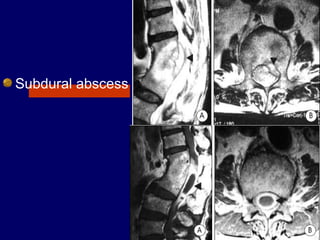

Subdural abscess

Magnetic resonance imaging

lumbosacral spine showing a

T1W isointense lesion

intradural extramedullary

lesion at D12-L1 level

measuring about 11.4 × 11.2

× 22.8 mm displacing the

conus and cauda (a and b).

On contrast (c and d) there is

heterogenous enhancement

with hypointense center and

peripheral enhancement